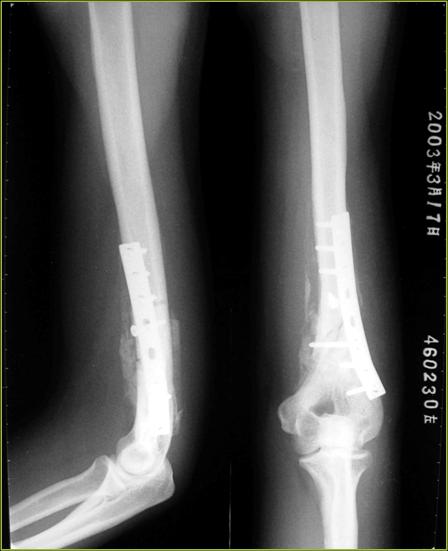

X-RAY:左肱骨干下端皮质破裂,内侧较大楔形骨块,骨折短端重叠移位,对位对线不良,余骨折未见异常。

患者入院后,卧床休养,进行各项入院检查未见手术禁忌,2003.2.17于全麻下进行左肱骨干骨折ORIF,取髂骨植骨术,术中输血400ml,液体2500ml。